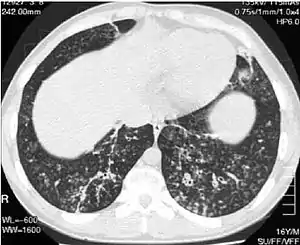

High-resolution computed tomography images of the lower chest in a 16-year-old boy with diffuse panbronchiolitis

The diagnosis of DPB requires analysis of the lungs and bronchiolar tissues, which can require a lung biopsy, or the more preferred high resolution computed tomography (HRCT) scan of the lungs.[7] The diagnostic criteria include severe inflammation in all layers of the respiratory bronchioles and lung tissue lesions that appear as nodules within the terminal and respiratory bronchioles in both lungs.[4] The nodules in DPB appear as opaque lumps when viewed on X-rays of the lung, and can cause airway obstruction, which is evaluated by a pulmonary function test, or PFT.[6] Lung X-rays can also reveal dilation of the bronchiolar passages, another sign of DPB. HRCT scans often show blockages of some bronchiolar passages with mucus, which is referred to as the "tree-in-bud" pattern.[7] Hypoxemia, another sign of breathing difficulty, is revealed by measuring the oxygen and carbon dioxide content of the blood, using a blood test called arterial blood gas. Other findings observed with DPB include the proliferation of lymphocytes (white blood cells that fight infection), neutrophils, and foamy histiocytes (tissue macrophages) in the lung lining. Bacteria such as H. influenzae and P. aeruginosa are also detectable, with the latter becoming more prominent as the disease progresses.[4][5] The white blood, bacterial and other cellular content of the blood can be measured by taking a complete blood count (CBC). Elevated levels of IgG and IgA (classes of immunoglobulins) may be seen, as well as the presence of rheumatoid factor (an indicator of autoimmunity). Hemagglutination, a clumping of red blood cells in response to the presence of antibodies in the blood, may also occur. Neutrophils, beta-defensins, leukotrienes, and chemokines can also be detected in bronchoalveolar lavage fluid injected then removed from the bronchiolar airways of individuals with DPB, for evaluation.[4][9]